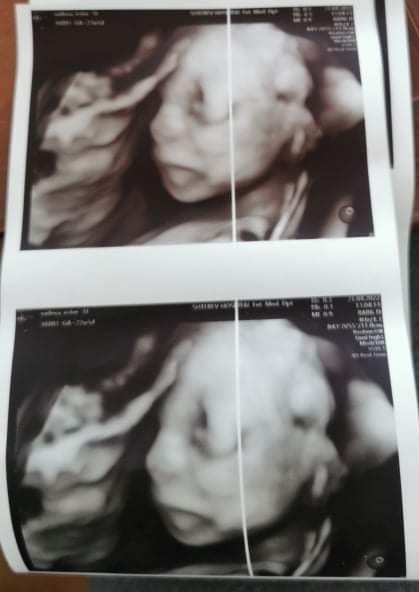

Аз сега се връщам от преглед при Чавеева, чаках близо два часа да влезна, но ме успккои, термина ми официално е 29.8.,каза че термина се изчислява на база на развитието през първия триместър Simple Smile) независимо, че по цикъл е 20.8. Не видя проблем с кръвопотока, бебка се развива чудесно и всичко и е наред. Качвам и една снимка Simple Smile